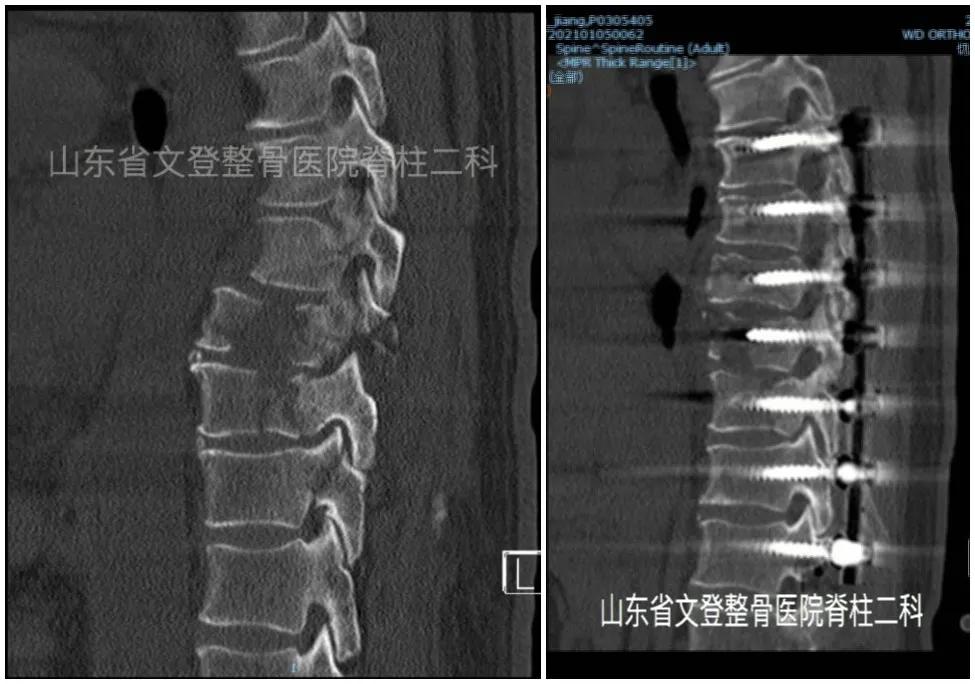

术前胸椎CT 术后胸椎CT